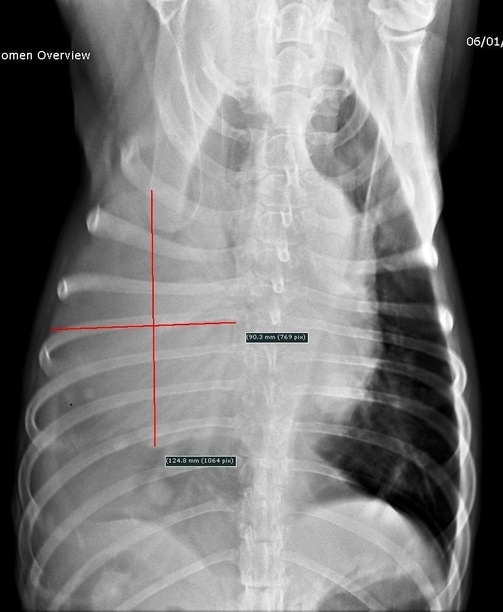

Au niveau du thorax, en revanche, une très volumineuse masse est présente dans le poumon droit dont le volume est supérieur à celui du cœur (12×9 cm sur la vue de face) ainsi que de plus petites masses métastatiques (fig. 12 et 13). Les propriétaires refusent d’aller plus loin dans les examens (scanner/biopsies…).

Plusieurs masses tumorales sont présentes dans le poumon droit dont la plus grosse a un diamètre de 12*9 cm sur la vue de face.